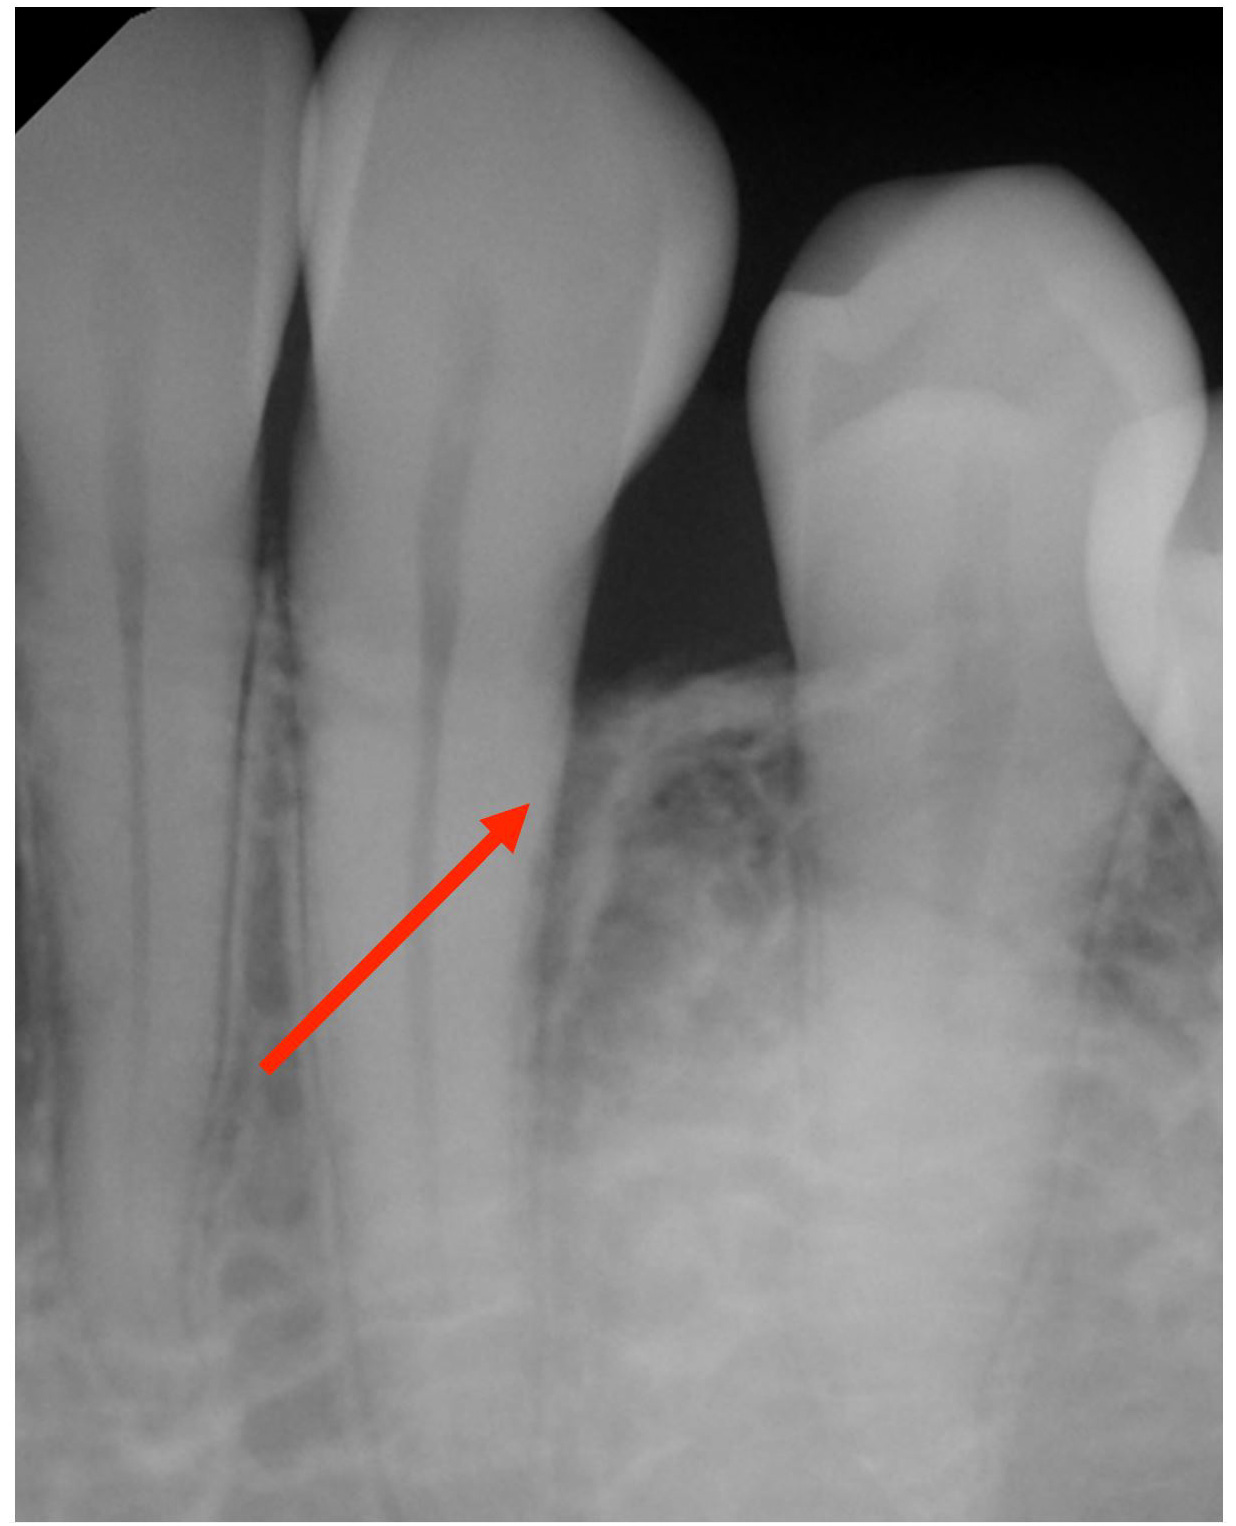

Laser for Periimplantitis

Laser Periodontal Treatment

*Follow-up x-rays 9-12 months after treatment